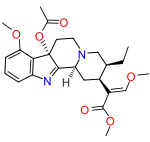

Oripavine derivatives

Thienorphine

- 7-PET

- Acetorphine

- Alletorphine (N-allyl-noretorphine)

- BU-48

- Buprenorphine

- Buprenorphine-3-glucuronide

- Cyprenorphine

- Dihydroetorphine

- Etorphine

- Homprenorphine

- 18,19-Dehydrobuprenorphine (HS-599)

- N-cyclopropylmethylnoretorphine

- Nepenthone

- Norbuprenorphine

- Norbuprenorphine-3-glucuronide

- Thevinone

- Thienorphine

Structures

| Oripavine derivatives | ||||

|---|---|---|---|---|

7-PET 7-PET |

Acetorphine Acetorphine |

Alletorphine Alletorphine |

BU-48 BU-48 |

Buprenorphine Buprenorphine |

Cyprenorphine Cyprenorphine |

Dihydroetorphine Dihydroetorphine |

Etorphine Etorphine |

Homprenorphine Homprenorphine |

18,19-Dehydrobuprenorphine 18,19-Dehydrobuprenorphine |

N-cyclopropylmethylnoretorphine N-cyclopropylmethylnoretorphine |

Nepenthone Nepenthone |

Norbuprenorphine Norbuprenorphine |

Thevinone Thevinone |

Thienorphine Thienorphine |